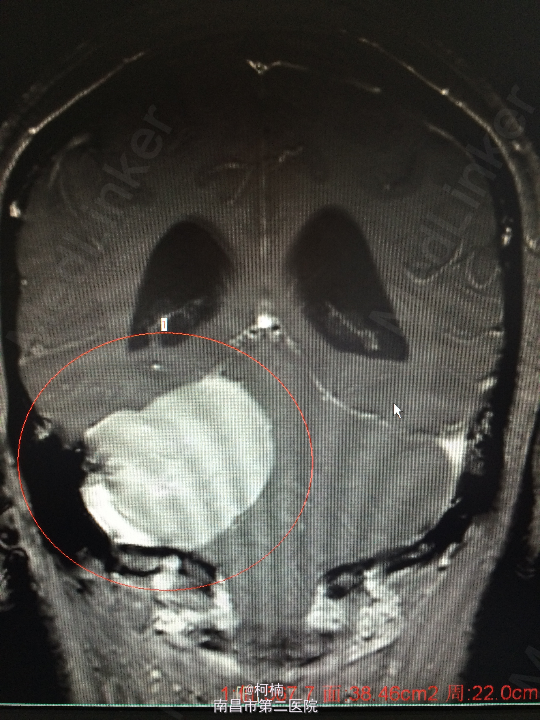

主诉:反复头晕、头痛伴呕吐及行走不稳10月余 病史:患者老年女性,55岁,10余月前开始出现头晕、头痛伴呕吐及行走不稳,无肢体乏力、肢体抽搐、意识障碍等不适,于当地医院诊治行头颅MR提示:右侧小脑角占位,考虑肿瘤。 查体:神经系统体查未见明显异常

查体:神经系统体查未见明显异常 辅助检查:头颅MR提示右侧桥小脑区占位性病变,考虑脑膜瘤。四脑室狭窄,变形,幕上脑室积水,小脑扁桃体疝

诊断:右侧小脑脑膜瘤 处理:先行介入栓塞肿瘤供血动脉,再行开颅手术治疗,术后予组织病理检查,提示:脑膜瘤